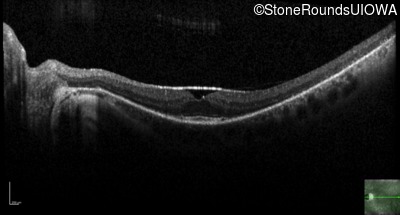

Optical Coherence Tomography - Right - 20/25 -2 sc

Exemplar / OCT Stack

OCT Stack